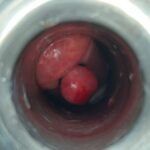

LASER LIAS FOR ANAL FISSURES AND BANDING OF HEMORRHOIDS